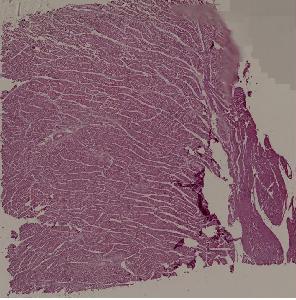

8.肉芽组织